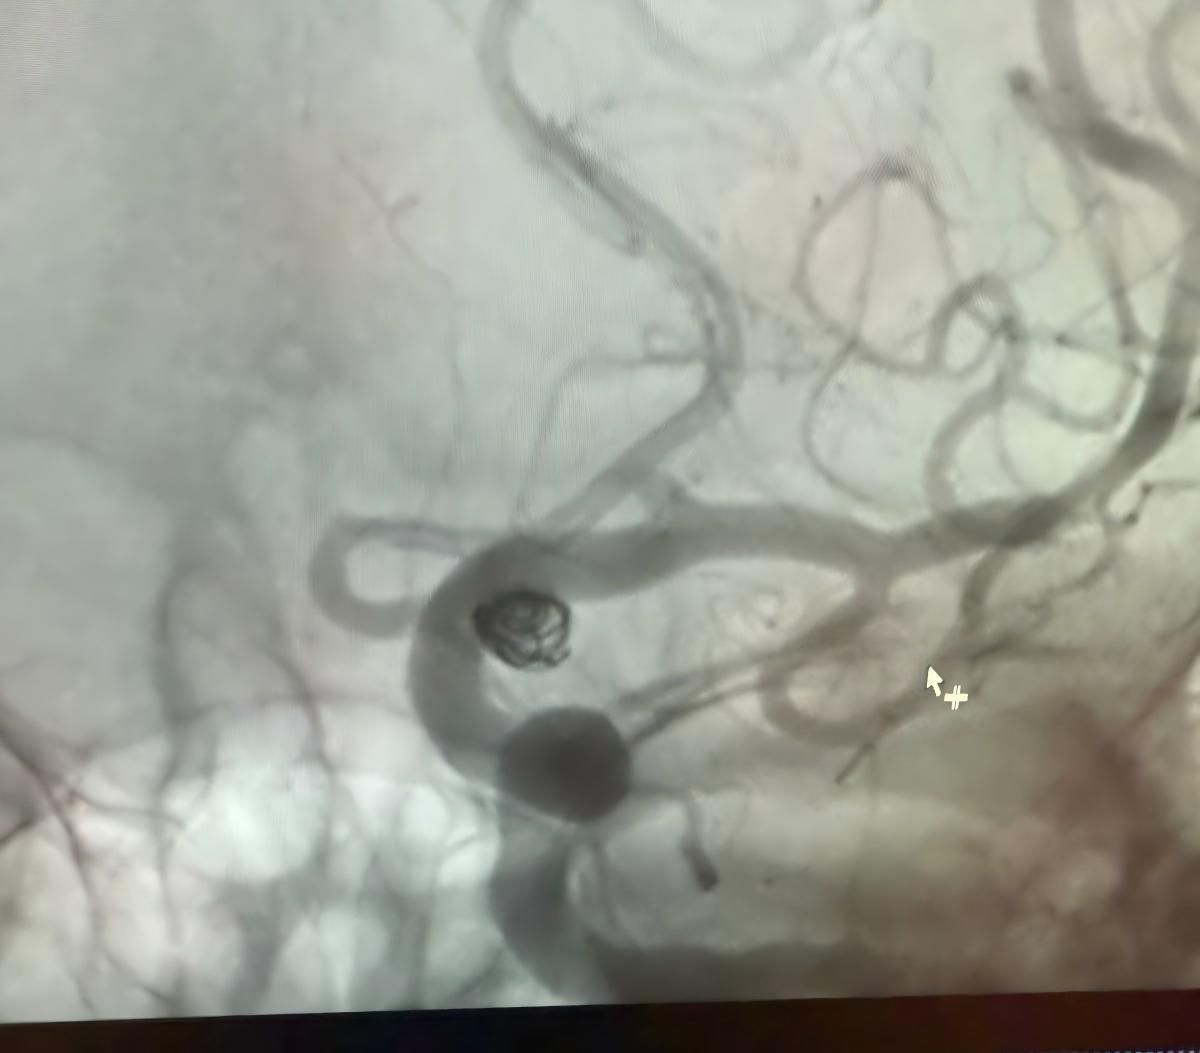

ホルヘ・ムティス博士が行った、メデジンのクリニカ・アルマ・マターでの最近の成功した手順を共有できることを嬉しく思います。

治療はNuvaを利用しました®流れのダイバーター (5.0-14 TJED-D) 、Perdenser®3Dコイル、およびFrepass®後部通信動脈動脈瘤用のマイクロカテーテル (TJMC18 Plus)。

Mutis博士は、デバイスの優れた視認性を強調し、回収がスムーズであると述べました。 彼は最終結果に大きな満足を表明した。